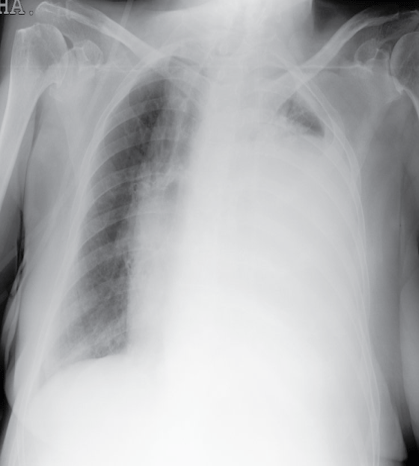

Moderate to massive effusion

Signs

- Tachypnea ⇒

- Limited movement of affected side ⇒

- Costal interspaces of affected side are wider ⇒

- Trachea shifts to opposite side ⇒

- Decreased vocal fremitus ⇒

- Stony Dullness ⇒

- Decreased or disappeared vesicular breath sound ⇒

- Pleural friction rub ⇒

- Abnormal bronchial breath sound in upper area of the fluid